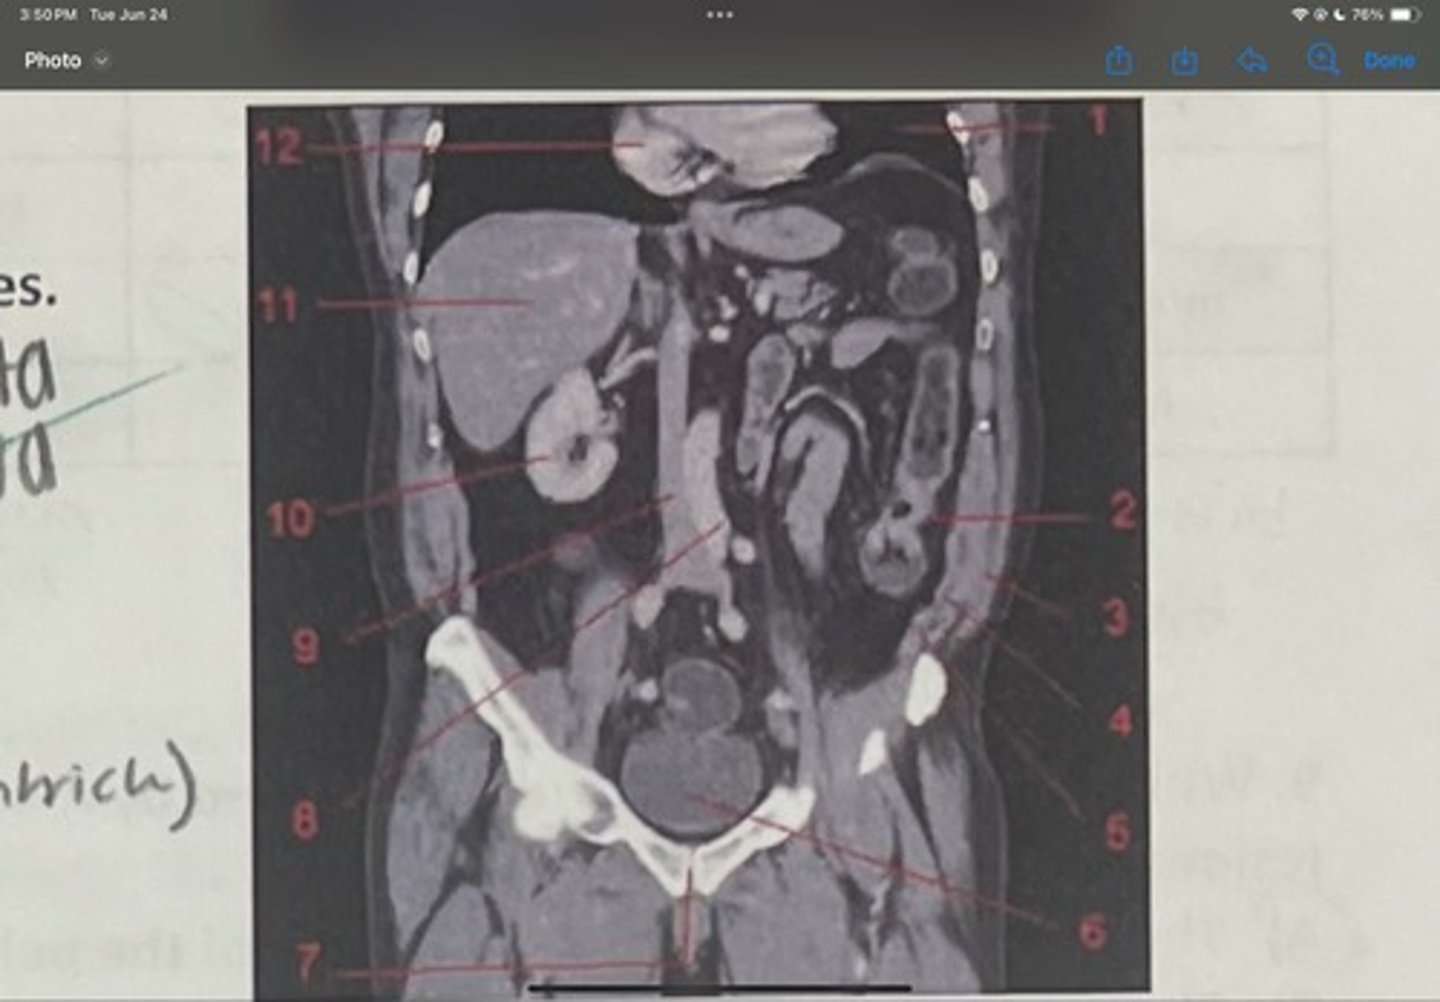

What is 1

Descending colon

What is 2

External oblique

What is 3

Internal obliques

What is 4

Transversus abdominis

What is 5

Bladder

What is 6

Pubic sysmphysis

What is 7

Abdominal aorta

What is 8

Inferior vena cava

What is 9

Right kidney

What is 10

Liver

What is 11

Heart (right ventricle)

What is 12

Subcostal nerve (T12)